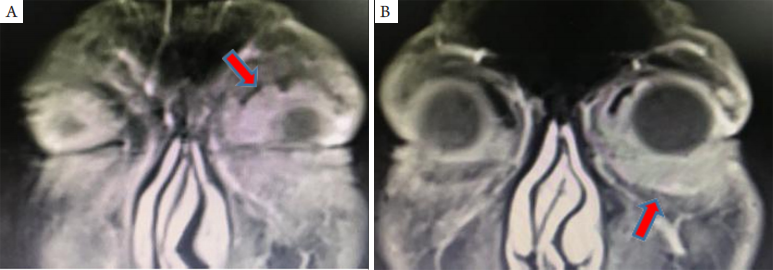

原发于眶隔前组织的眼睑淋巴瘤少见。一般为中老年人,表现为无痛性眼睑肿胀和肿块,病变可为结节状、条索状或眼睑弥漫增厚,可出现在上睑、下睑或上下睑同时发生(图1),以上睑多见[11-12],可为单个或多个病灶,亦可双眼同时或先后发生。影像学检查多可发现眼睑弥漫性增厚、或条形及团块状病变。眼睑型MALT淋巴瘤合并眼外淋巴瘤的发生率最高,故预后较差[11,13]

20230619102308_3634.png

图1 眼睑原发性 MALT 淋巴瘤增强 MRI

Figure 1 Enhanced MRI of primary MALT lymphoma of eyelid

(A)左上睑内上方占位; (B)左下睑占位病变中度强化。箭头示病变部位。

(A) An occupying lesion in the upper left eyelid; (B) Moderately enhanced left lower eyelid mass lesions. Arrows indicate the lession.